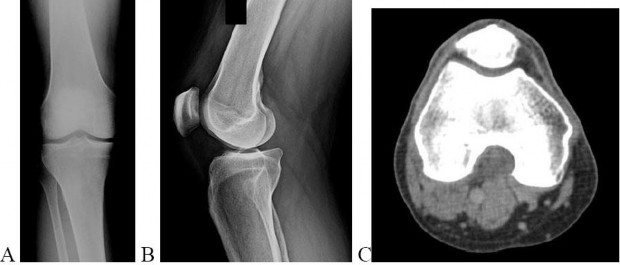

A 15-year-old male presents with deep knee pain awakening him at night. Radiographs show a permeative destructive lesion in the distal femoral metaphysis with a 'sunburst' periosteal reaction and Codman's triangle.

Biopsy confirms high-grade conventional osteosarcoma. What is the most critical prognostic factor for long-term overall survival in this patient?

Explanation

For localized high-grade osteosarcoma, the most important prognostic indicator is the histologic response to neoadjuvant chemotherapy. This is evaluated during the definitive resection. A 'good response' is typically defined as greater than 90% or 99% tumor necrosis. Patients who achieve this level of necrosis have a significantly improved disease-free and overall survival rate compared to 'poor responders' who have extensive viable tumor cells remaining.